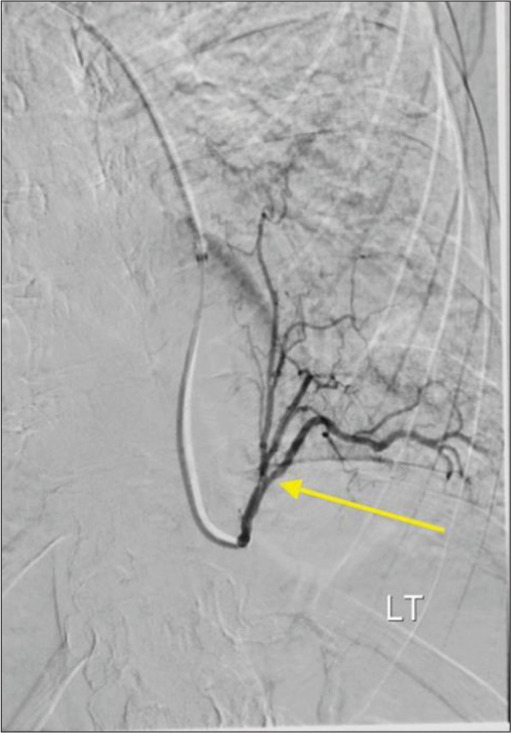

Pulmonary sequestration is a malformation of lung tissue such that a zone of pulmonary parenchyma exists in isolation from the bronchopulmonary tree. This condition is typically treated with surgical resection, but an increasing number of sequestrations are being treated with arterial embolization. We report interventions that were performed at two institutions on patients 53-70 years old. One patient presented with chronic cough and the two other patients presented with hemoptysis. Two of the cases were managed solely by endovascular embolization of the arteries supplying the pulmonary sequestration. In one patient, embolization was performed to debulk the sequestration, followed by surgical resection. These cases suggest transcatheter embolization may be an effective treatment in adult patients with symptomatic pulmonary sequestrations.